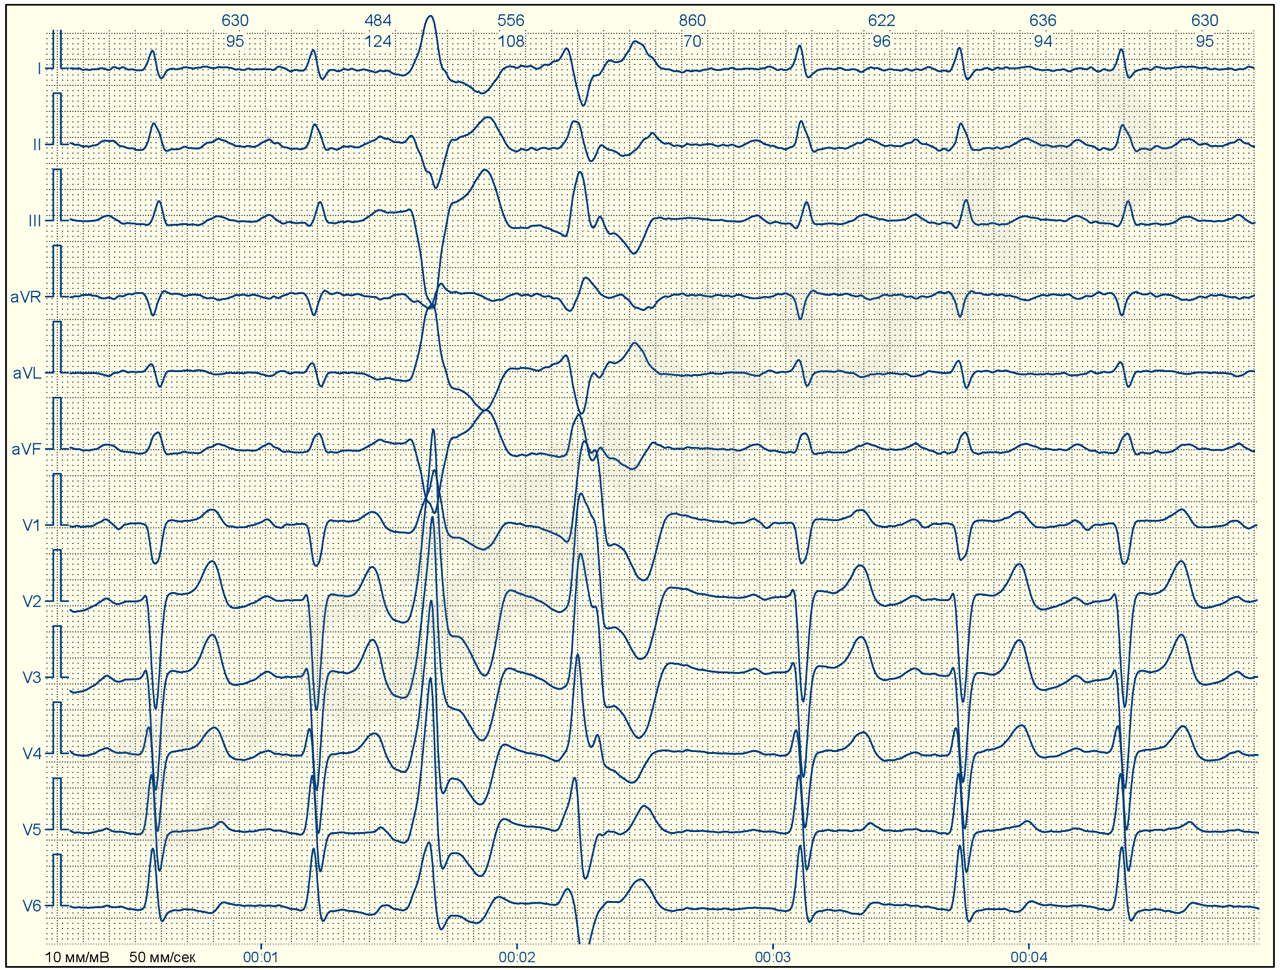

ЭКГ№10

Это еще одна ЭКГ, демонстрирующая вариант суправентрикулярной (в данном случае, узловой) экстрасистолы. Только тут, найти зубец ‘Р, не зная где искать, сложно. Это может показаться невероятным, но он тут есть и увидев его раз, вы будете насторожены впредь.

Эктопический очаг находится в нижних отделах АВ узла, а возможно и в стволе пучка Гиса (до разветвления ножек), так как возбуждение желудочков (QRS) начинается гораздо раньше, чем ретроградное возбуждение предсердий (отрицательный Р). Кроме того, это тот редкий 0,01% случаев, когда при наличии всех признаков суправентрикуляряной экстрасистолии, компенсаторная пауза оказывается полной.